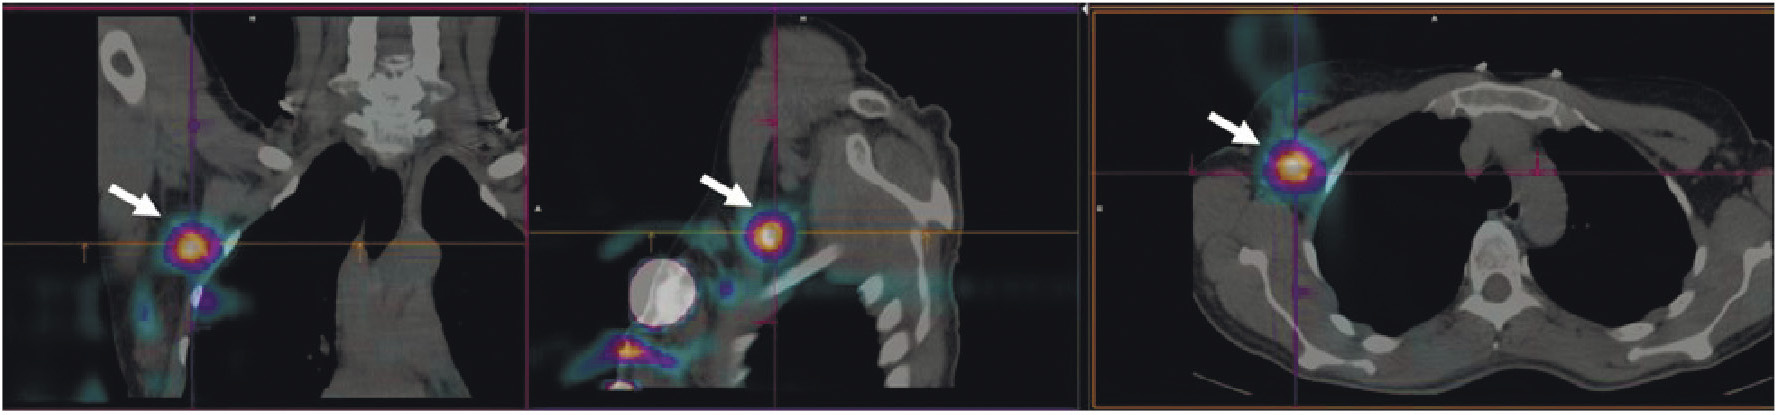

Имеющиеся в арсенале радиологов радиофармацевтические лекарственные препараты для визуализации СЛУ отличаются невысокой аккумуляцией (1.5–2% от введённой дозы). Поэтому в НИИ онкологии Томского НИМЦ и ТПУ был разработан оригинальный РФЛП на основе гамма-оксида алюминия “Сентискан, 99mТс” с высокими (около 12% от введённой дозы РФЛП) уровнем накопления в сторожевых лимфатических узлах [46]. Набор для его приготовления получил регистрационное удостоверение. Клинические испытания показали оптимальную фармакокинетику этого индикатора для интраоперационного выявления СЛУ и высокую эффективность при хирургических вмешательствах в случае рака шейки матки, рака эндометрия и злокачественных новообразований молочных желёз (рис. 9) [47, 48].

Рис. 9. ОФЭКТ/КТ пациентки с раком правой молочной железы после паратуморального введения РФЛП “Сентискан, 99mТс”